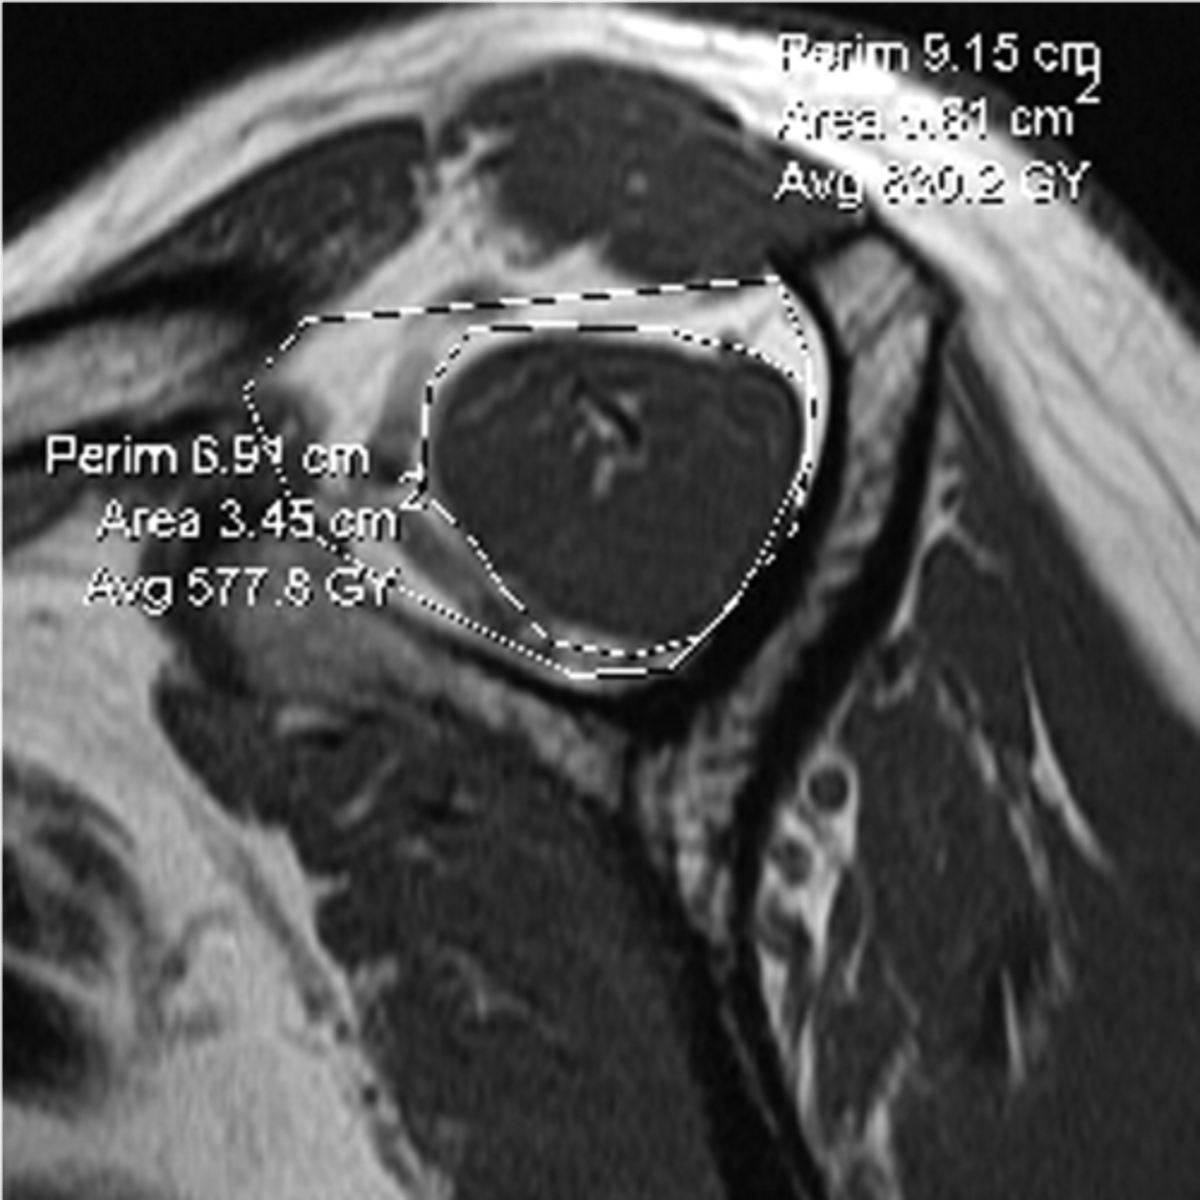

This system allows us to classify partial tears of the rotator cuff:

1 = Bursal-sided tear

3 = Intra-substance tear (in the middle of the tendon itself)

5 = Articular-sided tear

Note: we can also identify "delamination," where these fibers separate from one another, which would also be considered a partial tear

Why is understanding this image important?